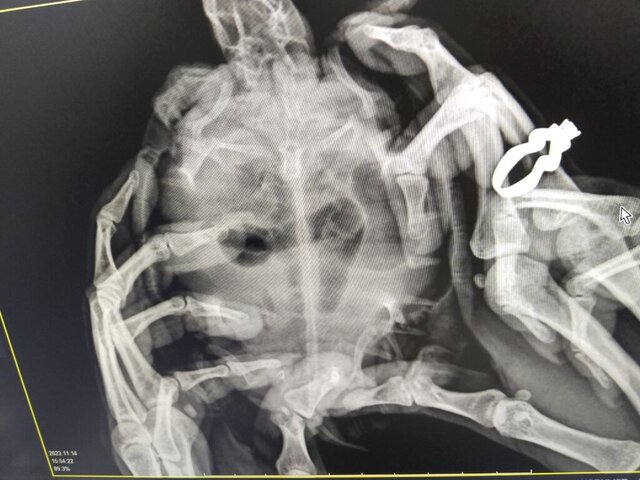

Константи Ваше имя: Константин Локация: Узбекистан Опубликовано: 14 ноября 2023 Автор Опубликовано: 14 ноября 2023 Сделали рентген, внутри ничего инородного они не увидели. Какие действия предпринять далее? Аппетит у черепахи отсутствует. Сейчас пробуем через пластиковый катетер прямым путем ввести еду. Не знаю правильно или нет. Что посоветуете делать?

Константи Ваше имя: Константин Локация: Узбекистан Опубликовано: 14 ноября 2023 Автор Опубликовано: 14 ноября 2023

Консультанты moth Ваше имя: Мария Локация: Москва Опубликовано: 14 ноября 2023 Консультанты Опубликовано: 14 ноября 2023 @Константи а вторую проекцию не делали? по этой проекции у неё газы и в желудке и в жкт

Константи Ваше имя: Константин Локация: Узбекистан Опубликовано: 15 ноября 2023 Автор Опубликовано: 15 ноября 2023 Нет, только так делали. У нас в Узбекистане специалистов вообще нет. Подскажите пожалуйста что делать?

Консультанты moth Ваше имя: Мария Локация: Москва Опубликовано: 15 ноября 2023 Консультанты Опубликовано: 15 ноября 2023 @Константи нужно выводить газы, у неё очень сильно раздут желудок и кишечник. Вот это тёмное на снимке - это всё раздутые кишки и желудок. Вам нужно купить Эспумизан и внутривенный катетер (попросите продать в любой ветклинике). Выпаивать зондом 0.02мл Эспумизана раз в сутки. Сколько дней черепаха не ест? если больше 10, то можно также зондом докармливать. Нужно Рептомин развести до состояния воды и выпоить 0.5мл для начала. Также добавьте вибротерапию - положите черепаху в небольшой контейнер без воды и поставьте на сильно вибрирующий прибор на 10 минут, можно на телефон в режиме максимальной вибрации. И 1-2 раза в день заставляйте плавать по аквариуму. Но следите за одышкой, если начнёт дышать ртом - оставить в покое. 1